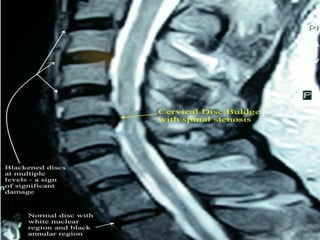

MRI lumbar spine;

 Helps to visualize the disc, nerve root, thecal sac.

 Compression of nerve root.